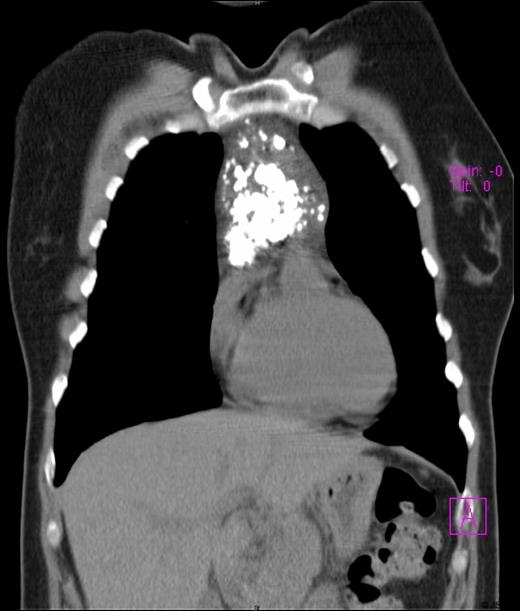

A 45-year-old female presented with symptoms of gastroesophageal reflux. Her past medical history included hypothyroidism and endometriosis. The patient reported fatigue over several months, but denied any chest pain, fever, dyspnea, cough or weight loss. Physical examination was unremarkable. She underwent a double-contrast upper GI series which revealed no abnormalities in the oesophagus or stomach but was suggestive of an intra-thoracic mass. Chest radiograph noted a heavily calcified mass in the anterior mediastinum. Computed tomography (CT) scan of the thorax revealed a well defined mass of mixed density with speckled calcifications located in the antero-superior mediastinum. The lesion extended from the sternal notch to the level of the aortic root (Figures 1a and 1b). Laboratory tests including β-HCG, α-fetoprotein, CEA, LDH and TSH were all within normal limits and pulmonary function tests were normal. Preoperatively, the working diagnosis was a thymoma, although not typical in appearance, and thus surgical resection was planned. The operation was performed through a median sternotomy. A radical “en-bloc” resection of the tumour, mediastinal fat, thymus, pericardium and pleura was carried out. There was no evidence of tumour dissemination in the pericardium or pleural cavities or metastatic lymphadenopathy. Macroscopically, the tumour was completely resected with negative margins. The patient had an uneventful postoperative course and was discharged one week after surgery. A 24 month follow-up has shown no recurrence of the disease.

Preoperative chest computed tomography scan revealing a large mediastinal mass - Coronal view